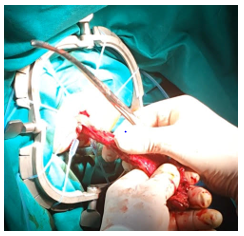

Meckel’s Diverticulum in a 6-Year-Old Girl. A Rare Presentation of Intussusception and Volvulus of Small Bowel

George-Charles Camilleri, Glenn Costa and Mohamed Shoukry. 13(8): 01-04.